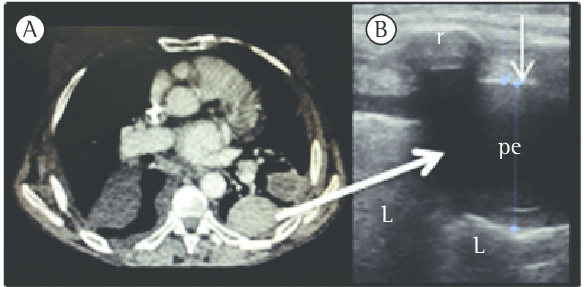

Chest PA & right decubitus view show loculated right ...

Chest PA & right decubitus view show loculated right ... from www.researchgate.net